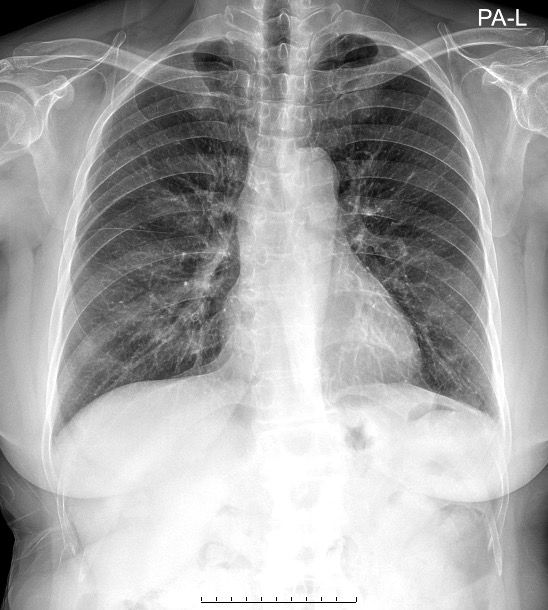

내과 엑스레이 소견 봐주세요..!!

내일 정밀 검사할 거긴 한데, 70대 여성으로 왼쪽 팔까지 통증 및 누워있을 때 통증이 더 심해지고 소화 불량, 토할 것 같은 느낌이 있습니다. 동네 병원 갔더니 큰 병원 가보라고 해서.. 이 사진 상으로 의심되는 게 있을까요?

올리신 사진의 엑스레이 소견에는 특별히 심각한 문제가 있어 보이거나 하지는 않습니다. 심장의 크기도 정상 범위로 보이며, 폐의 염증이나 기흉 등의 활동성 병변이 의심스럽거나 하지 않습니다. 엑스레이 소견만으로는 딱히 문제가 있고 어떠한 문제가 있는지 등 여부를 파악 및 판단하기 어렵겠습니다.